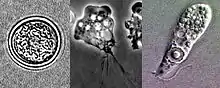

| Lifecycle stages of Naegleria fowleri: flagellate, trophozoite and cyst (seen from upper left to lower left to right) | |

Naegleria fowleri is a thermophilic, free-living amoeba. It is found in warm and hot freshwater ponds, lakes and rivers, and in the very warm water of hot springs.[15] As the water temperature rises, its numbers increase. The amoeba was identified in the 1960s in Australia but appears to have evolved in the United States.[16] N. fowleri occurs in three forms – as a cyst, a trophozoite (ameboid), and a biflagellate. It does not form a cyst in human tissue, where only the amoeboid trophozoite stage exists. The flagellate form can exist in the cerebrospinal fluid.